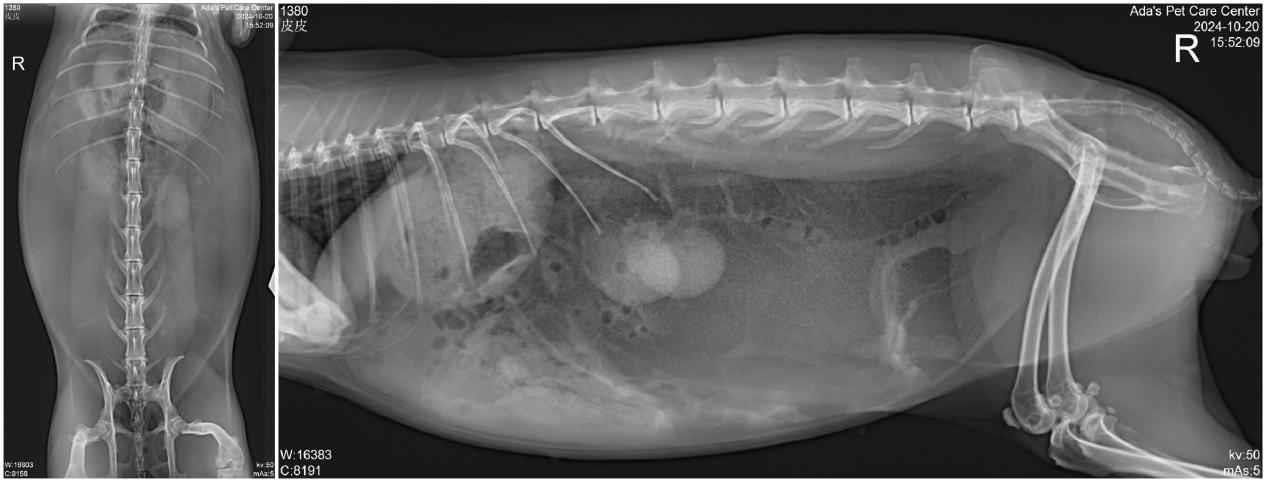

🐰 In this case, obesity was the main culprit. X-ray imaging revealed a large amount of fat accumulation in the abdominal cavity, confirming that excessive weight had placed too much strain on the feet, leading to pododermatitis.